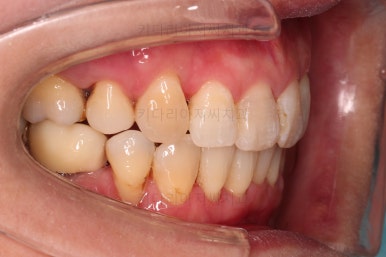

동래임플란트교정 마무리 되었습니다.

임플란트 머리도 잘 올라갔고, 치열도 가지런해졌으며 교합이나 중앙선도 적절히 마무리 되었습니다.

전후 비교를 해보겠습니다.

웃는 모습이 매우 우아해지셨어요.

미소가 굉장히 예뻐지셨습니다.

더군다나 예상한대로 발치교정으로 입을 많이 넣었음에도 팔자주름이나 피부처짐이 없이 잘 마무리 되었습니다.